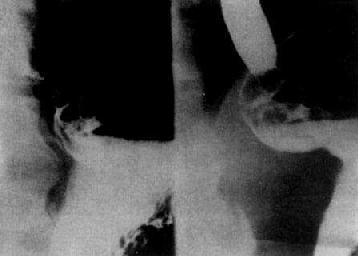

许多球部溃疡不易显出龛影,但如有恒久的球部变形,也能作出溃疡的诊断(图4-2-14)。球部变形主要是由于瘢痕收缩、粘膜水肿和痉挛所致,可以是山字形、三叶形、葫芦形等。有时在变形的球部仍可显示龛影。球部溃疡愈合后,龛影消失,变形可继续存在。

图4-2-14 十二指肠球部溃疡(变形)

球部呈不同形状的变形,有的其中可见龛影(↓)